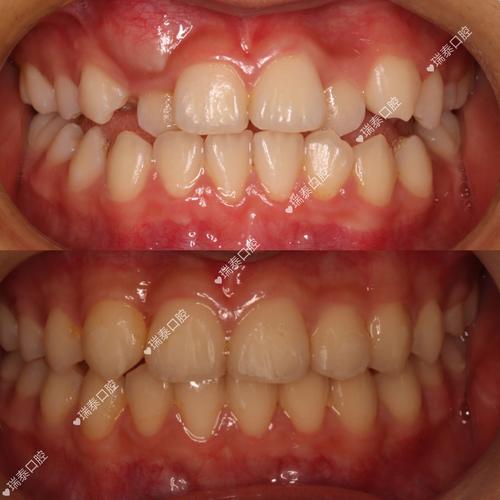

- 功能改善: 有效解决牙齿排列不齐、咬合关系异常等问题,恢复良好的咀嚼功能,改善发音。

- 美学提升: 矫正后的牙齿排列整齐,笑容更美观,对面部轮廓(如改善“凸嘴”、“地包天”等)也有积极影响,提升自信心。

- 案例丰富: 积累了海量的成功案例,涵盖各种类型的错颌畸形,为患者提供了丰富的参考。